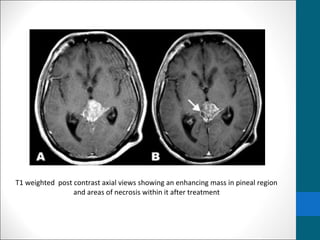

MRI IMAGING

•T1 - isointense to hypointense to adjacent brain

•T2 isointense to adjacent brain

•Areas of cyst formation or necrosis my be present

•T1 C+ (Gd) - vivid heterogeneous enhancement

T1 weighted post contrast axial views showing an enhancing mass in pineal region

and areas of necrosis within it after treatment

T1 weighted postcontrast axial views showing an enhancing mass in pineal region and areas of necrosis within it after treatment